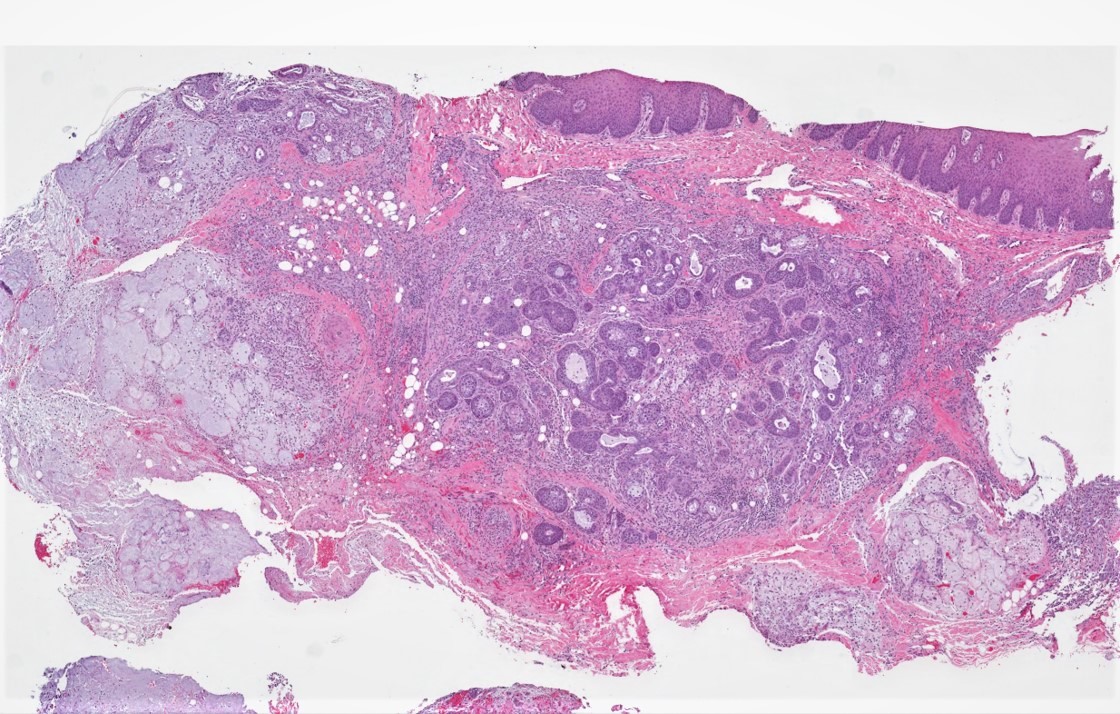

Microscopic (histologic) description

- Squamous metaplasia of ductal structures and acini with preservation of the salivary lobular architecture is an essential feature, according to World Health Organization (see WHO classification-oral cavity & oropharynx)

- Necrosis / infarction of acini characterized by loss of nuclei and cell borders with or without zones of spilled mucin

- Pseudoepitheliomatous hyperplasia with generally bland cytology or keratinocytic regenerative atypia

- Reactive, myxocollagenous background stroma

- Surface ulceration, granulation tissue and subacute inflammation may be present

- Has been conceptualized by 5 histologic stages of development and evolution: infarction, sequestration, ulceration, repair and healing (Int J Oral Surg 1982;11:283)

Microscopic (histologic) images